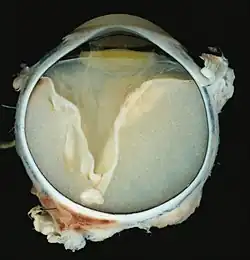

Grossly, retinal detachment and yellowish subretinal exudate containing cholesterol crystals are commonly seen.